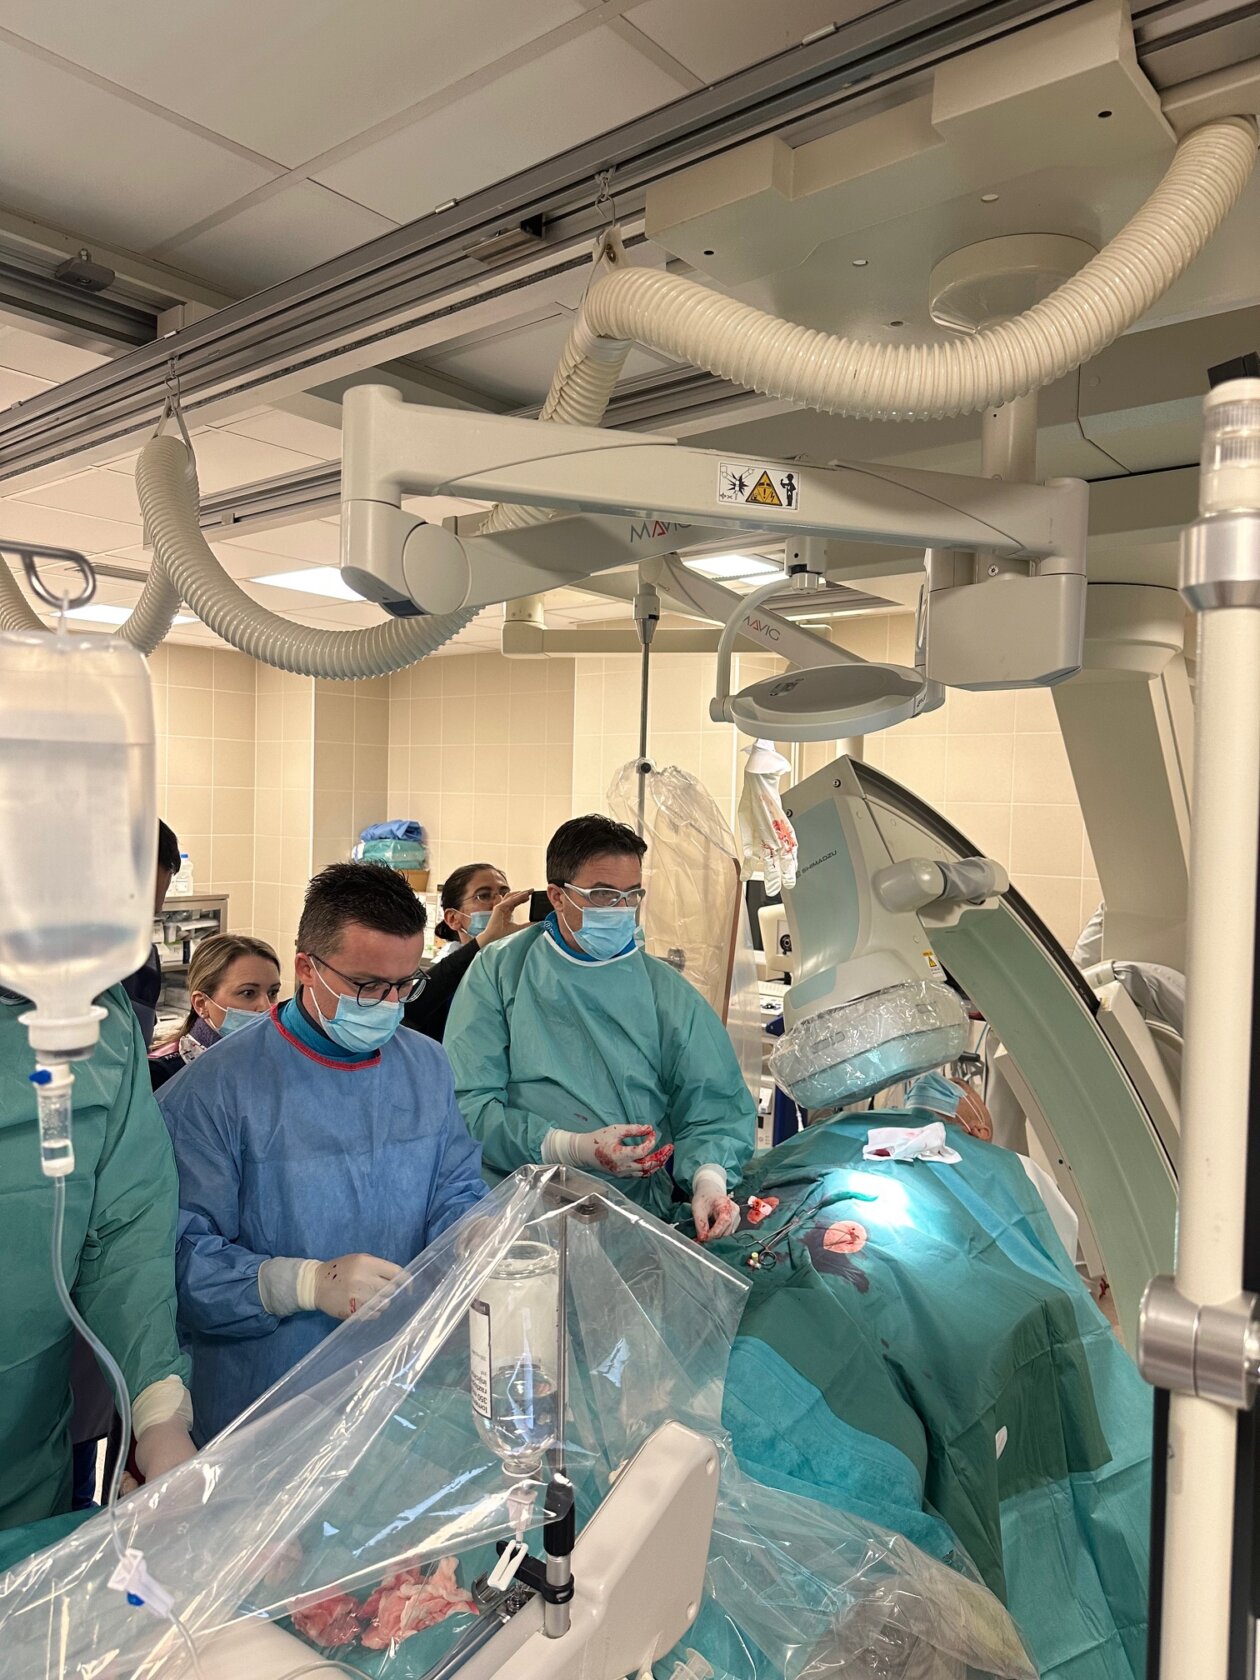

Na Odjelu intervencijske kardiologije, pod vodstvom dr. med. Mihajla Kovačića, specijalista interne medicine i subspecijalista kardiologije, izvedena je prva kompleksna intervencija uz pomoć novog uređaja za potporu srčane funkcije – Impella CP.

Zahvat je izveden uz stručnu podršku prof. dr. sc. Joška Buluma, dr. med., jednog od vodećih hrvatskih kardiologa, a označava velik iskorak u modernizaciji invazivnog liječenja najtežih srčanih bolesnika.